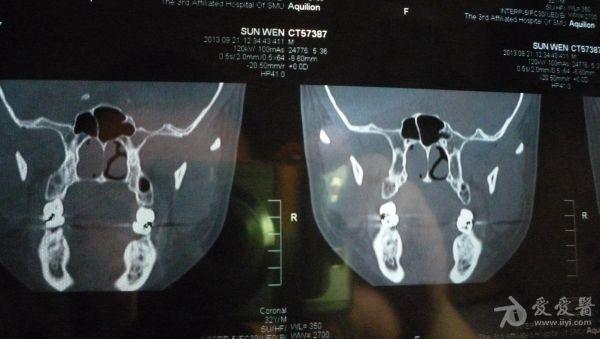

CT结果是右侧上颌窦及部分筛窦窦腔内见稍高密度影填充,CT值约21U,窦壁骨质未见破坏征象;鼻腔后部亦见少量稍高密度影填充;左侧上颌窦、筛窦及蝶窦、额窦未见明显异常。CT图片见附件。医生说我的右边鼻窦都被软组织堵死了,必须要做手术清楚后再做病理分析看是良性还是恶性。

想请问下医生:CT图片上右边的上颌窦内的稍高密度影,是软组织还是液体的几率大些呢